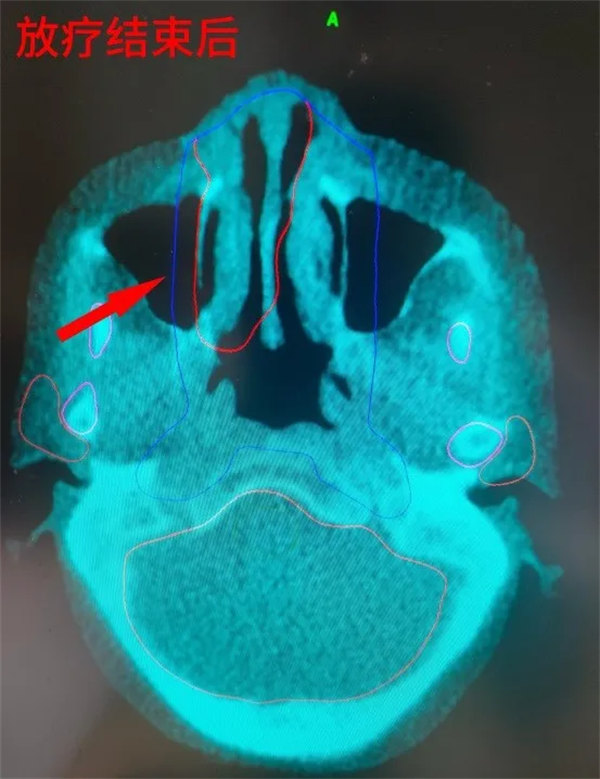

68歲的趙阿姨,2月前因“鼻塞及視物模糊”就診入院,經全面檢查后確診為右側鼻腔NK/T細胞淋巴瘤,明確診斷后血液腫瘤內科主任朱暉組織醫護團隊進行多次討論,并請放射治療科張世衡副主任醫師會診綜合評估,根據患者年齡、心肺功能、腫瘤分期、體能狀況,最終制定以放療序貫化療的治療方案,放射治療科醫護團隊立即為患者做好放療前準備:制模定位、勾畫靶區、制定計劃,并于第二天下午實施放療,在放療過程中,主管醫生侯蕊及張世衡醫生密切關注患者病情變化,為患者及家屬做好解釋,消除患者的消極情緒。經過25次的放療,患者鼻腔腫瘤明顯消退,趙阿姨高興地說:“自己鼻子不堵了,看東西也清楚了,對于后續的治療相當有信心”。